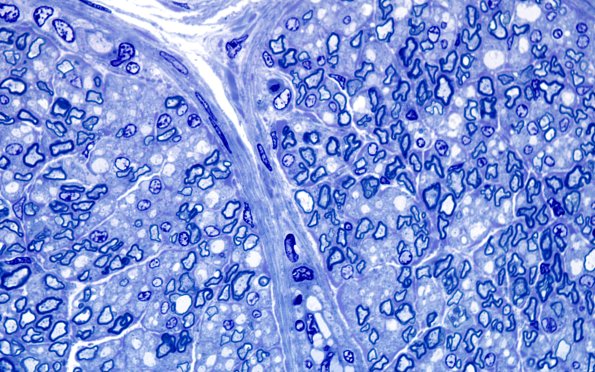

Washington University Experience | PERIPHERAL NEUROPATHY | 1 NORMAL NERVE ANATOMY | 6 Infant Peripheral Nerve | 3A4 Infant, 4wk age (Case 3) Plastic 100X 1

Higher magnification of one of the fascicles shown in #3A1. (Plastic section)